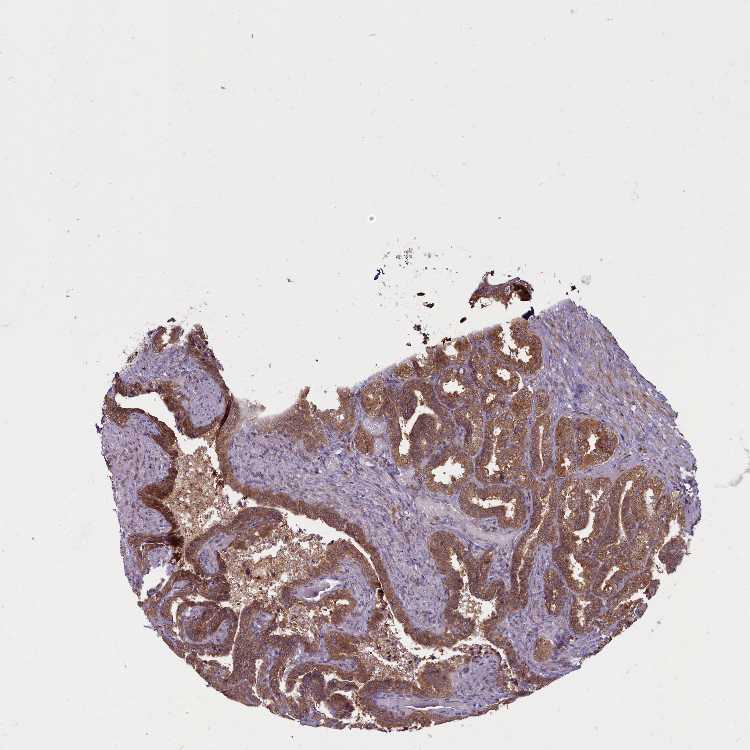

SEMINAL VESICLE - Antibody stainingi

Antibody staining in the annotated cell types in the current human tissue is reported as not detected, low, medium, or high, based on conventional immunohistochemistry profiling in selected tissues. This score is based on the combination of the staining intensity and fraction of stained cells.

Each image is clickable and will lead to virtual microscopy that enables deeper exploration of all samples and also displays staining intensity scores, fraction scores and subcellular localization as well as patient and tissue information for each sample.

Antibody HPA041188

Glandular cells High